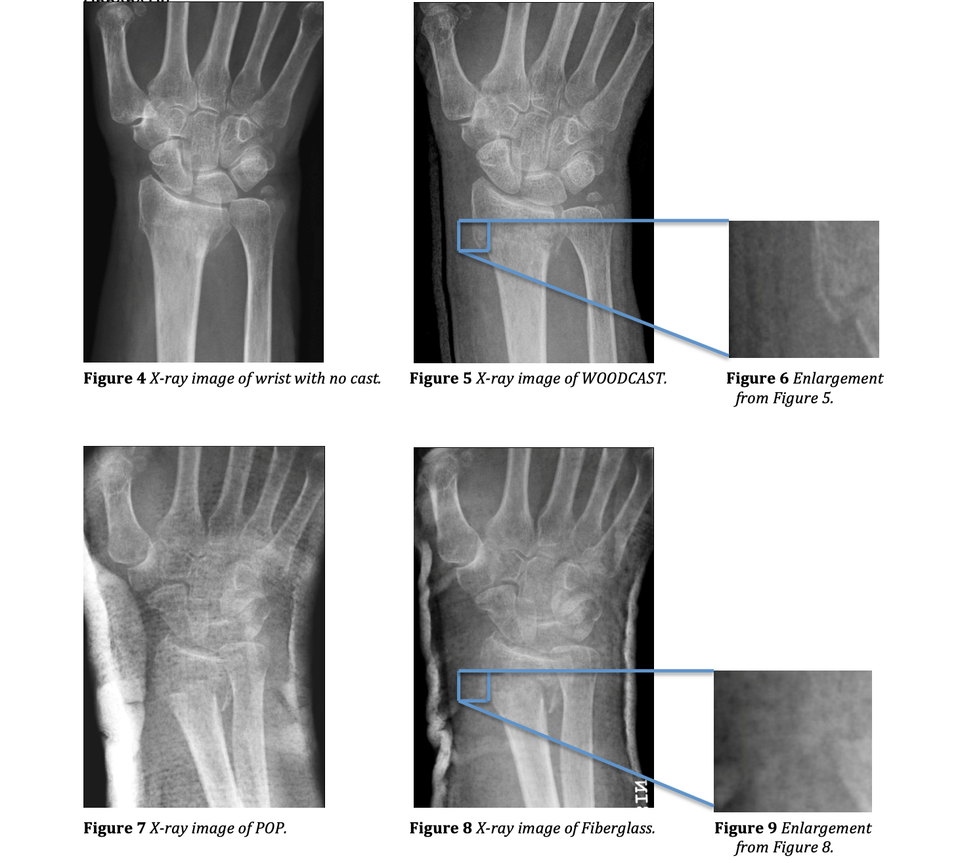

Woodcast is X-ray transparent. See below a comparison of Plaster-of-paris (left), fiberglass (middle) and Woodcast casts.